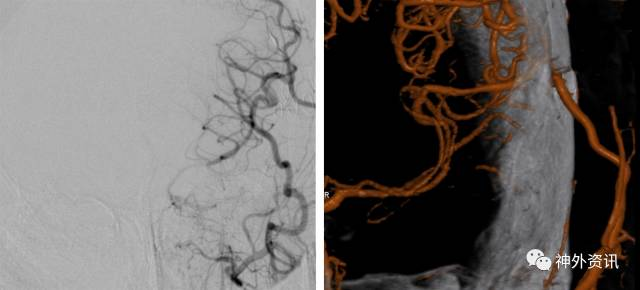

图12. 患者出院后定期随诊复查导管造影或者CTA来评价搭桥的通畅性。此例行左侧STA-MCA搭桥的患者其桥血管保持畅通(右图为三维重建影像)。